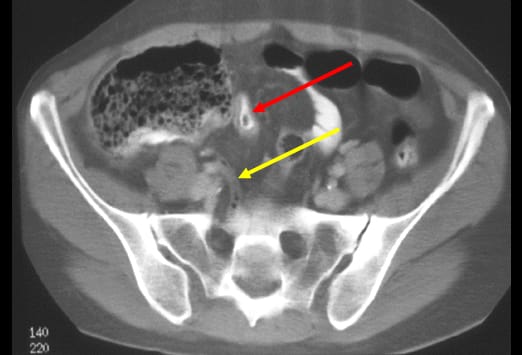

Diese Abbildung zeigt einen Appendikolithen (weißer Pfeil) mit einem großen Abszess (blau gestrichelte Linie), der einzelne Lufteinschlüsse enthält (roter Pfeil). Es zeigen sich angrenzend weitere entzündliche Veränderungen im Bereich des terminalen Ileums (gelber Pfeil). Eine Perforation stellt die schwerste Form der fortgeschrittenen Appendizitis dar, da es hier zu einer Infektion der Bauchhöhle kommt. Eine Perforation kann somit einen Abszess, eine Peritonitis und einer Sepsis zu Folge haben.